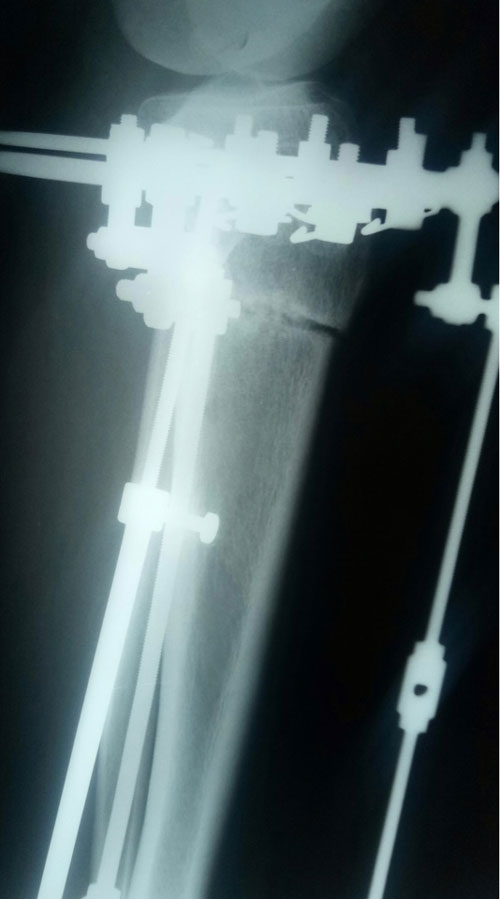

Дата операции- 30.11.2018г.

Дата снятия аппаратов - 12.03.2019г.

Срок сращения - 100 дней.